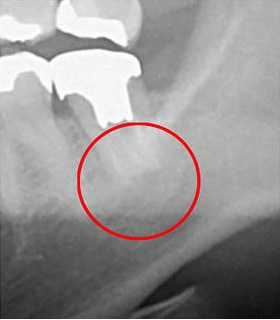

次の比較画像は、同じ歯をCTとレントゲンで撮影したものです。

左の画像がCT、右がレントゲンです。

左のCTでは黒い影が見えます。この黒い影は、歯の根の炎症です。右のレントゲンには写っていません。レントゲンだけの検査の場合、この炎症は見逃されてしまうということです。

CTを使うことで、初期の炎症も見逃さずに、適切な診断ができます。